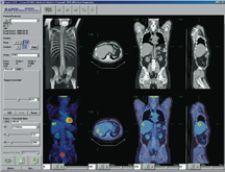

C4’s PET/CT plug-in displays images and information in a PACS-like reading context across dual monitors. “Radiologists reporting PET/CT cases are often looking for information and functionality beyond the capabilities of a standard PACS workstation. Capabilities such as image registration, image fusion, hot spot analysis and SUV are particular to PET/CT imaging. With C4 however, this functionality can be incorporated into a standard PACS workstation,” explained Clark. “In this example, the workflow value of C4 is fairly clear – a radiologist does not need to move from a PACS reporting workstation to a separate PET/CT workstation. Comprehensive diagnostic support can be provided on any PACS workstation throughout the healthcare enterprise. One can similarly see how this technology benefits a radiologist working in areas that require five or six different clinical applications to be used regularly.”

In anticipation of all specialty imaging workstations requiring PACS, HIS, 3-D tools, remote access and interoperability with other departments, physicians and hospitals, HERMES has developed RAPID CD, an application for the display and analysis of PET, NM, CT, MRI and ultrasound exams. Designed for users who do not have direct access to an image server, it features image fusion capability, shows three orthogonal views simultaneously across modalities, has image reorientation, MIP movie data, splash display, volume of interest (VOI) generation and standard uptake value (SUV) calculation, and can be used on a PC.